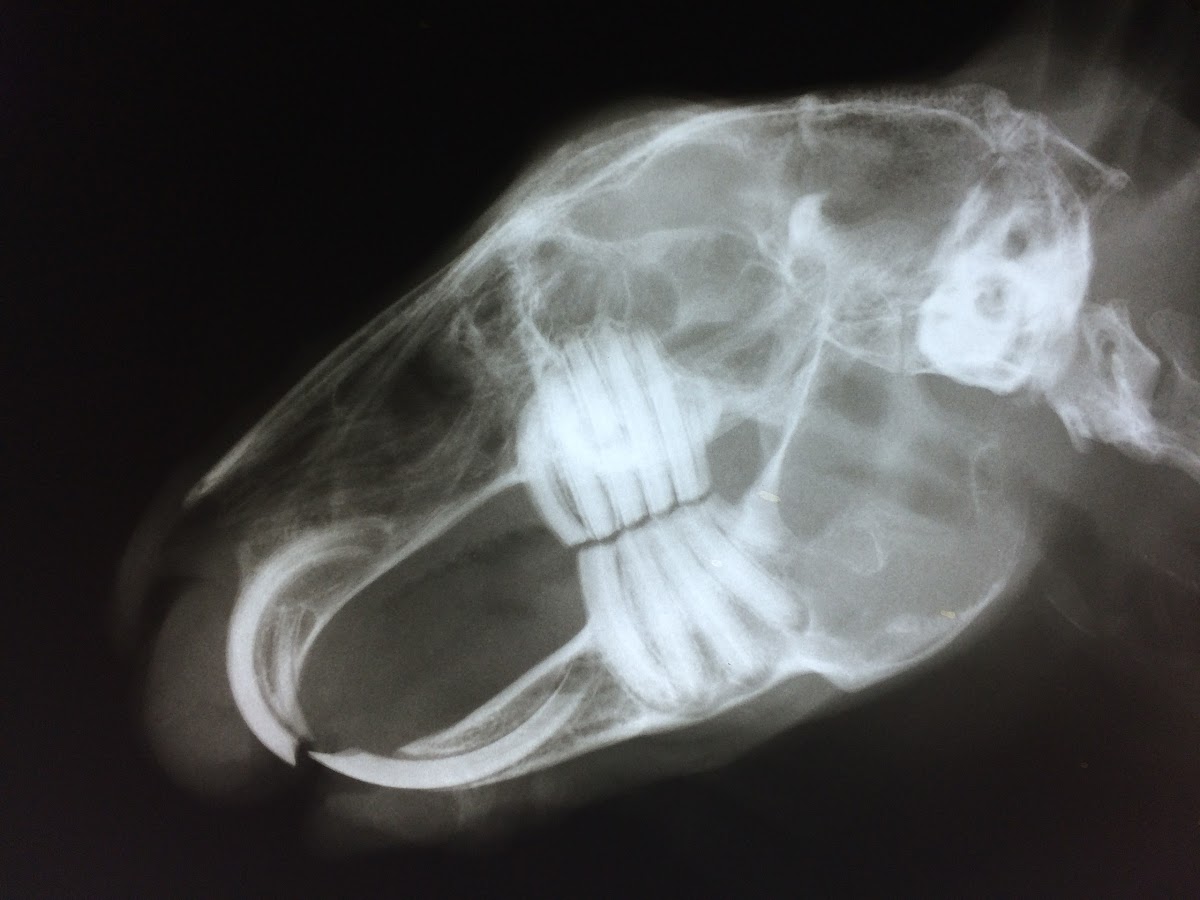

Ich bin Anfang 2023 mit meinen beiden aus dem Tierschutz adoptierten Kaninchen in die Praxis von Frau Dr. Wirth gekommen. Zuvor war ich bei einem anderen Tierarzt in Behandlung. Meine Kaninchen waren beide qualzuchtbedingte „Zahnkandidaten“ und es war dazu gekommen, dass einem von ihnen die Schneidezähne gezogen werden mussten. Leider begab es sich, dass besagter Tierarzt dabei sehr inkompetent handelte, sodass ich Bibble einige Tage post-OP mit einem extremen Kieferabszess in die Praxis von Frau Dr. Wirth brachte. Zu diesem Zeitpunkt war es bereits fast zu spät.

Das Praxisteam um Frau Dr. Wirth hat Bibble das Leben gerettet. Monatelang, anfangs jeden zweiten Tag, stand ich regelmäßig zur Wundversorgung auf der Matte. Frau Dr. Wirth hat auch noch einmal persönlich operiert. Nach über einem Dreivierteljahr war das unmöglich Scheinende geschafft. Heute ist Bibble ein zwar schneidezahnloses, aber quietschgesundes und fröhliches junges Kaninchen. Auch mein zweites Kaninchen war mit schweren chronischen Magendarmproblemen kein leichter Fall, aber hier war sie immer gut aufgehoben. Auch wenn sie mittlerweile an ihrer Krankheit verstorben ist, weiß ich, dass Frau Dr. Wirth und ihr Team maßgeblich dazu beigetragen haben, ihr Leben leichter zu machen und zu verlängern.

In dieser Praxis ist der Service überragend. Man fühlt sich zu keinem Zeitpunkt fehl am Platz oder „abgefrühstückt“, die Stimmung ist immer freundschaftlich und es wird alles in der Macht Stehende für die Tiere getan. Ich empfehle die Praxis explizit an Heimtierhalter*innen und bin sehr froh, eine kaninchenkundige Tierärztin in meiner Nähe gehabt zu haben. Sollte ich noch einmal ein Tier adoptieren, werde ich zu 100% wieder hierherkommen. Anbei ein paar Fotos in Erinnerung an Marshi und von Bibble in seinem neuen Zuhause🤍

Nachdem seit meinem letzten Besuch einige Zeit ins Land gegangen ist, möchte ich nun auch endlich einmal eine Bewertung schreiben. Ich bin Anfang 2023 mit meinen beiden aus dem Tierschutz adoptierten Kaninchen in die Praxis von Frau Dr. Wirth gekommen. Zuvor war ich bei einem anderen Tierarzt in Behandlung. Meine Kaninchen waren beide qualzuchtbedingte „Zahnkandidaten“ und es war dazu gekommen, dass einem von ihnen die Schneidezähne gezogen werden mussten. Leider begab es sich, dass besagter Tierarzt dabei sehr inkompetent handelte, sodass ich Bibble einige Tage post-OP mit einem extremen Kieferabszess in die Praxis von Frau Dr. Wirth brachte. Zu diesem Zeitpunkt war es bereits fast zu spät. Das Praxisteam um Frau Dr. Wirth hat Bibble das Leben gerettet. Monatelang, anfangs jeden zweiten Tag, stand ich regelmäßig zur Wundversorgung auf der Matte. Frau Dr. Wirth hat auch noch einmal persönlich operiert. Nach über einem Dreivierteljahr war das unmöglich Scheinende geschafft. Heute ist Bibble ein zwar schneidezahnloses, aber quietschgesundes und fröhliches junges Kaninchen. Auch mein zweites Kaninchen war mit schweren chronischen Magendarmproblemen kein leichter Fall, aber hier war sie immer gut aufgehoben. Auch wenn sie mittlerweile an ihrer Krankheit verstorben ist, weiß ich, dass Frau Dr. Wirth und ihr Team maßgeblich dazu beigetragen haben, ihr Leben leichter zu machen und zu verlängern. Es kam zu einem großen Streit mit dem vorherbehandelnden Tierarzt, in dem Frau Dr. Wirth mich bis zum Schluss professionell unterstützt und beraten hat. In dieser Praxis ist der Service überragend. Man fühlt sich zu keinem Zeitpunkt fehl am Platz oder „abgefrühstückt“, die Stimmung ist immer freundschaftlich und es wird alles in der Macht Stehende für die Tiere getan. Ich empfehle die Praxis explizit an Heimtierhalter*innen und bin sehr froh, eine kaninchenkundige Tierärztin in meiner Nähe gehabt zu haben. Sollte ich noch einmal ein Tier adoptieren, werde ich zu 100% wieder hierherkommen. Anbei ein paar Fotos in Erinnerung an Marshi und von Bibble in seinem neuen Zuhause🤍